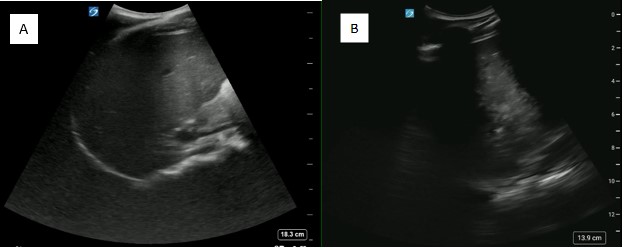

Ipsilateral hemidiaphragm paralysis is possible, as the phrenic nerve runs atop the anterior scalene muscle (Figure 4). Therefore, this block should be avoided in any patient with respiratory compromise, and a bilateral block should be avoided. Given the known complication of diaphragm paralysis, a short acting analgesic is suggested to avoid prolonged paralysis. Additionally, with any nerve block, careful consideration must be taken to account for maximum local anesthetic doses to avoid LAST.

May2025-Pedi Interscalene_Fig 4.jpgFigure 4. Coronal FAST view that can be utilized to assess for ipsilateral diaphragm paralysis (A) and its resolution (B)

Ipsilateral hemidiaphragmatic paralysis is a known complication of interscalene nerve block that providers should expect to occur. However, it is tolerated well in a patient without known respiratory compromise or pre-existing respiratory conditions. This paralysis is temporary, so it is advisable to select a short-acting analgesic that is only required for the duration of the procedure. The presence of this complication can be confirmed with POCUS, in the traditional coronal FAST view. The resolution prior to discharge can also be confirmed with POCUS, as in this case (Figure 4).